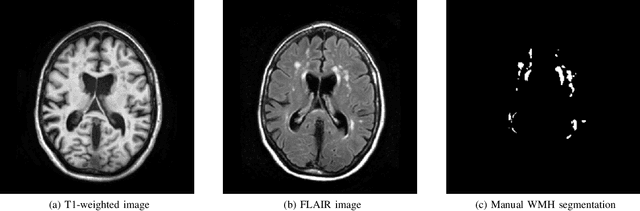

Abstract:Quantification of cerebral white matter hyperintensities (WMH) of presumed vascular origin is of key importance in many neurological research studies. Currently, measurements are often still obtained from manual segmentations on brain MR images, which is a laborious procedure. Automatic WMH segmentation methods exist, but a standardized comparison of the performance of such methods is lacking. We organized a scientific challenge, in which developers could evaluate their method on a standardized multi-center/-scanner image dataset, giving an objective comparison: the WMH Segmentation Challenge (https://wmh.isi.uu.nl/). Sixty T1+FLAIR images from three MR scanners were released with manual WMH segmentations for training. A test set of 110 images from five MR scanners was used for evaluation. Segmentation methods had to be containerized and submitted to the challenge organizers. Five evaluation metrics were used to rank the methods: (1) Dice similarity coefficient, (2) modified Hausdorff distance (95th percentile), (3) absolute log-transformed volume difference, (4) sensitivity for detecting individual lesions, and (5) F1-score for individual lesions. Additionally, methods were ranked on their inter-scanner robustness. Twenty participants submitted their method for evaluation. This paper provides a detailed analysis of the results. In brief, there is a cluster of four methods that rank significantly better than the other methods, with one clear winner. The inter-scanner robustness ranking shows that not all methods generalize to unseen scanners. The challenge remains open for future submissions and provides a public platform for method evaluation.